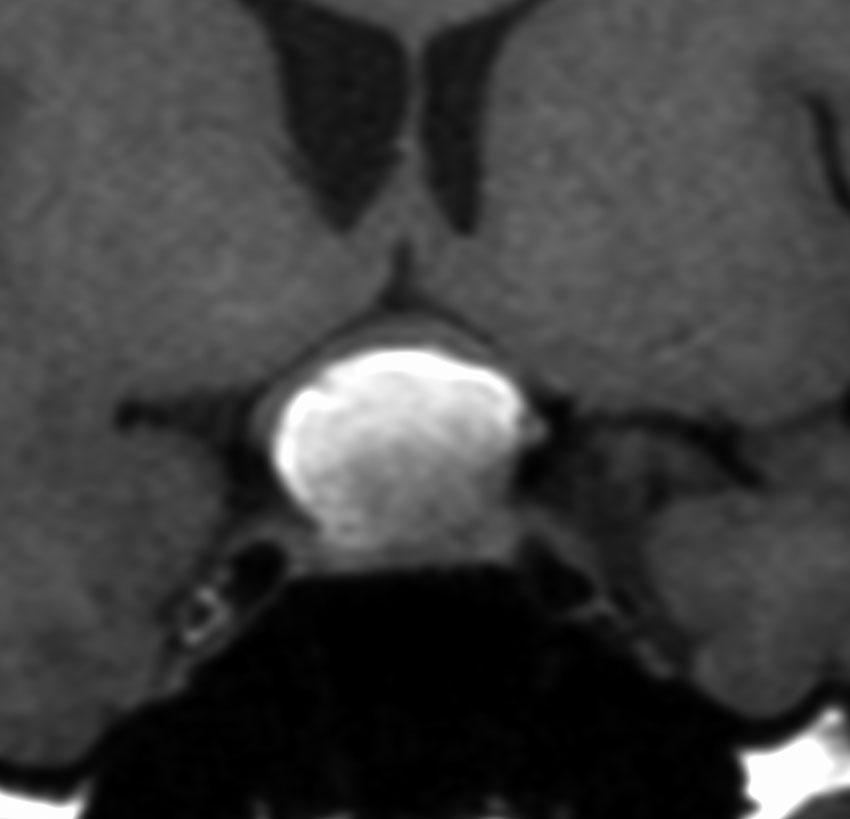

29歳の女性が高プロラクチン血症による月経不順で発症しました。視野検査では両耳側半盲が認められました。

手術所見では,多量のコレステリン結晶が流出しました。腫瘍実質は硬く正常下垂体との剥離はできませんでした。黄色肉芽種の可能性もあるので,あ全摘出にとどめて手術を終了しました。T2強調画像で黒い低信号の縁取りがあり内部に不均一なのう胞内容液が見えるのが特徴とも言えます。

3年後の画像です。腫瘍の再燃増大はありませあん。視野は正常化して,下垂体機能も正常化しホルモン補充はありません。